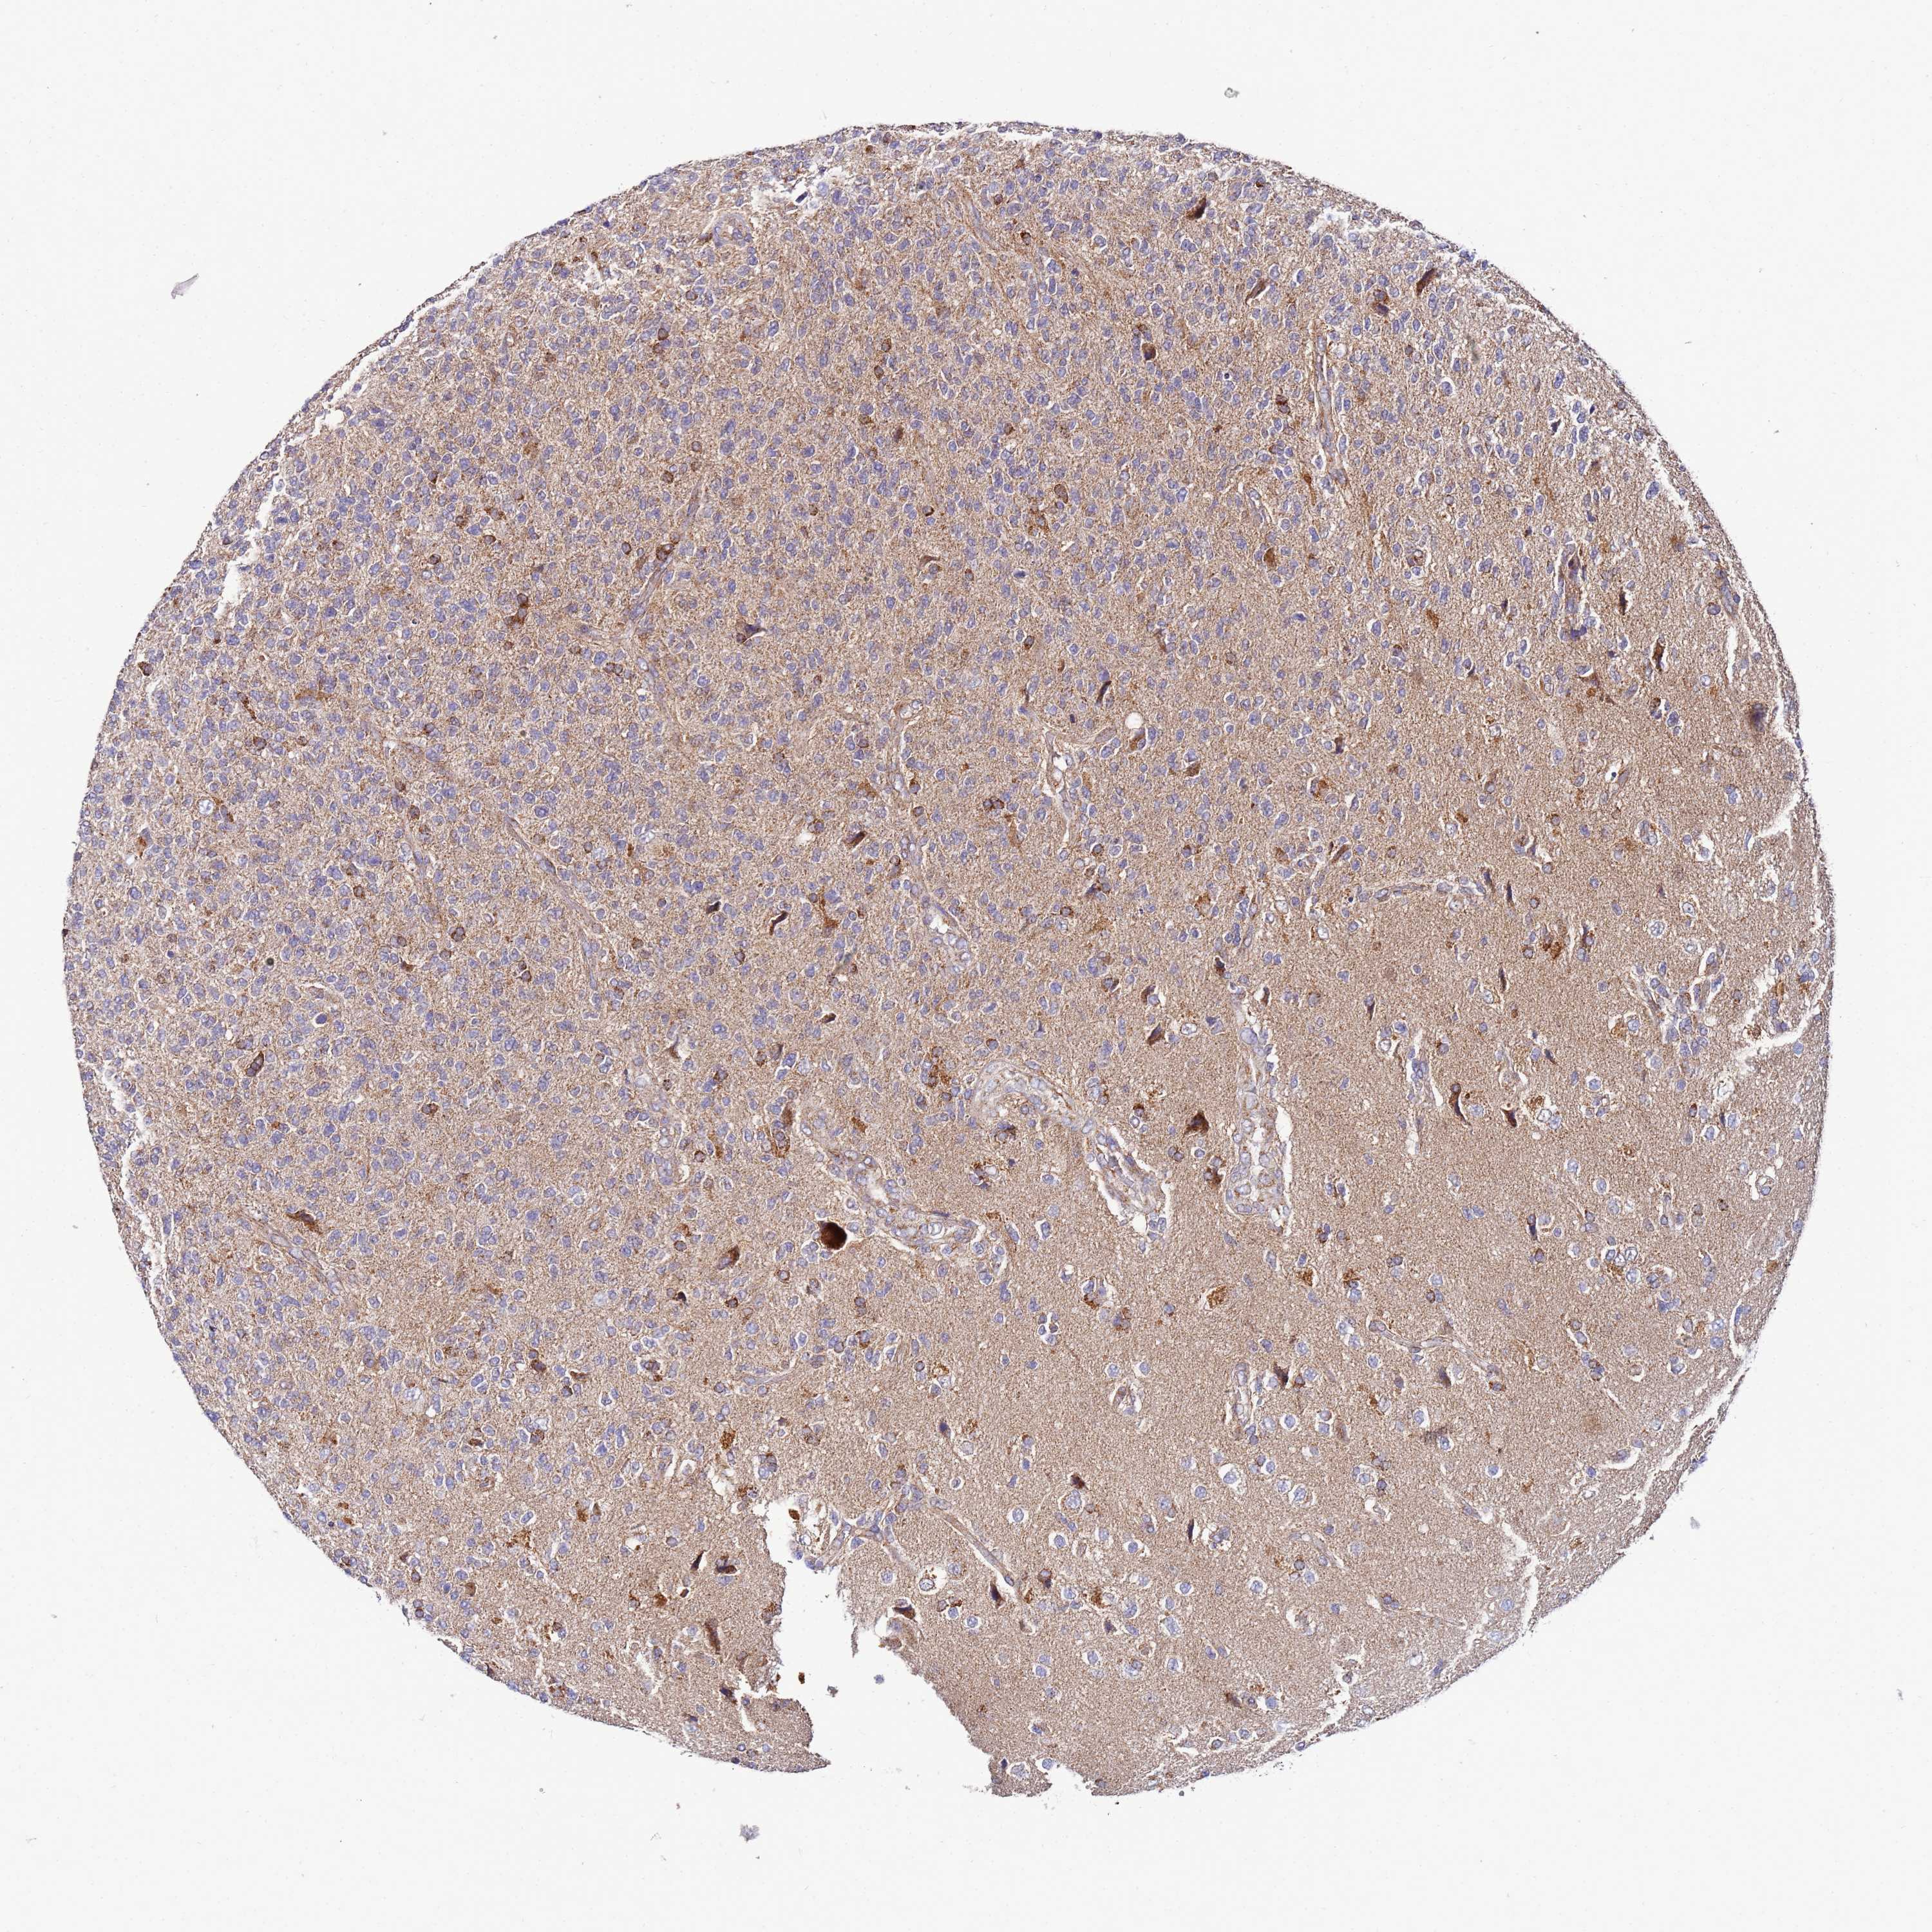

GLIOMA - Protein expressioni

A mouse-over function shows sample information and annotation data. Click on an image to view it in a full screen mode. Samples can be filtered based on level of antibody staining by selecting one or several of the following categories: high, medium, low and not detected. The assay and annotation is described here.

Note that samples used for immunohistochemistry by the Human Protein Atlas do not correspond to samples in the TCGA dataset.

Antibody stainingi

Antibody staining in the annotated cell types in the current human tissue is reported as not detected, low, medium, or high, based on conventional immunohistochemistry profiling in selected tissues. This score is based on the combination of the staining intensity and fraction of stained cells.

Each image is clickable and will lead to virtual microscopy that enables deeper exploration of all samples and also displays staining intensity scores, fraction scores and subcellular localization as well as patient and tissue information for each sample.

Antibody HPA042145

Antibody HPA044987

Antibody CAB045971

Antibody CAB045972

Staining

High

Medium

Low

Not detected

Intensity

Strong

Moderate

Weak

Negative

Quantity

>75%

75%-25%

<25%

None

Location

Nuclear

Cytoplasmic/membranous

Cytoplasmic/membranous,nuclear

Glioma, malignant, Low grade

Glioma, malignant, High grade